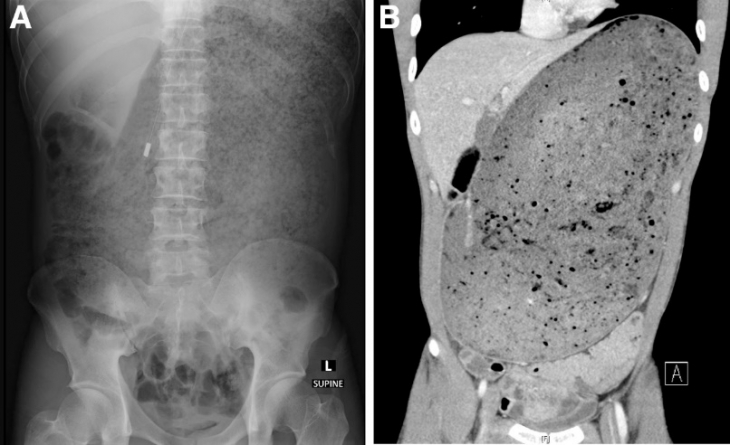

병원에서 복부 CT 촬영을 한 결과 A씨의 위와 십이지장은 섭취한 음식물로 인해 거대하게 늘어나 있었다. 소화되지 않은 음식물이 주변의 장기를 압박하며 췌장이 으스러져 있었다. 또한 혈액 속 총 백혈구 수와 혈청 크레아티닌, 혈청 아밀라제 수치도 심각하게 높았다.

공개된 남성의 복부 CT 사진에는 배꼽 바로 위부터 어깨 부근까지 음식물로 가득 차있는 모습이 고스란히 담겼다.